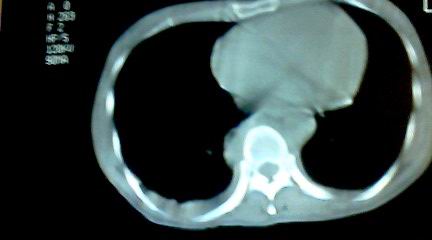

标题: CT25218:请教!胸部CT,胸8椎体骨质破坏,伴周围软组织肿。 [打印本页]

标题: CT25218:请教!胸部CT,胸8椎体骨质破坏,伴周围软组织肿。

患者,女41岁,肢体乏力。

两肺上叶继发性肺结核;胸椎结核并椎旁寒性脓肿形成。

胸椎结核并椎旁寒性脓肿形成。

支持两肺上叶继发性肺结核;胸椎结核并椎旁寒性脓肿形成

两肺上叶继发性肺结核;胸椎结核并椎旁寒性脓肿形成